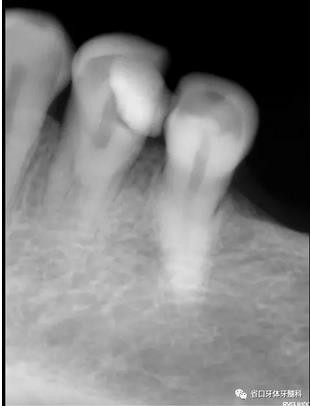

圖1:術(shù)前X線片:34遠(yuǎn)中高密度影及髓,疑似雙根管

1、以單根管為主的下頜第一前磨牙,由于發(fā)育上的特點,根管系統(tǒng)存在較大變異,可能是最難以進(jìn)行根管清潔和成型的一組牙齒,常因為忽略了雙根管及多根管的存在,造成遺漏根管發(fā)生。本病例中,34的術(shù)前X線片可見,主根管影像突然消失,提示我們可能存在多根管,CBCT的有助于我們了解根管分叉位置和根管的彎曲情況,全程顯微鏡下治療有助于我們進(jìn)行髓底探查及進(jìn)行有效預(yù)備根充。